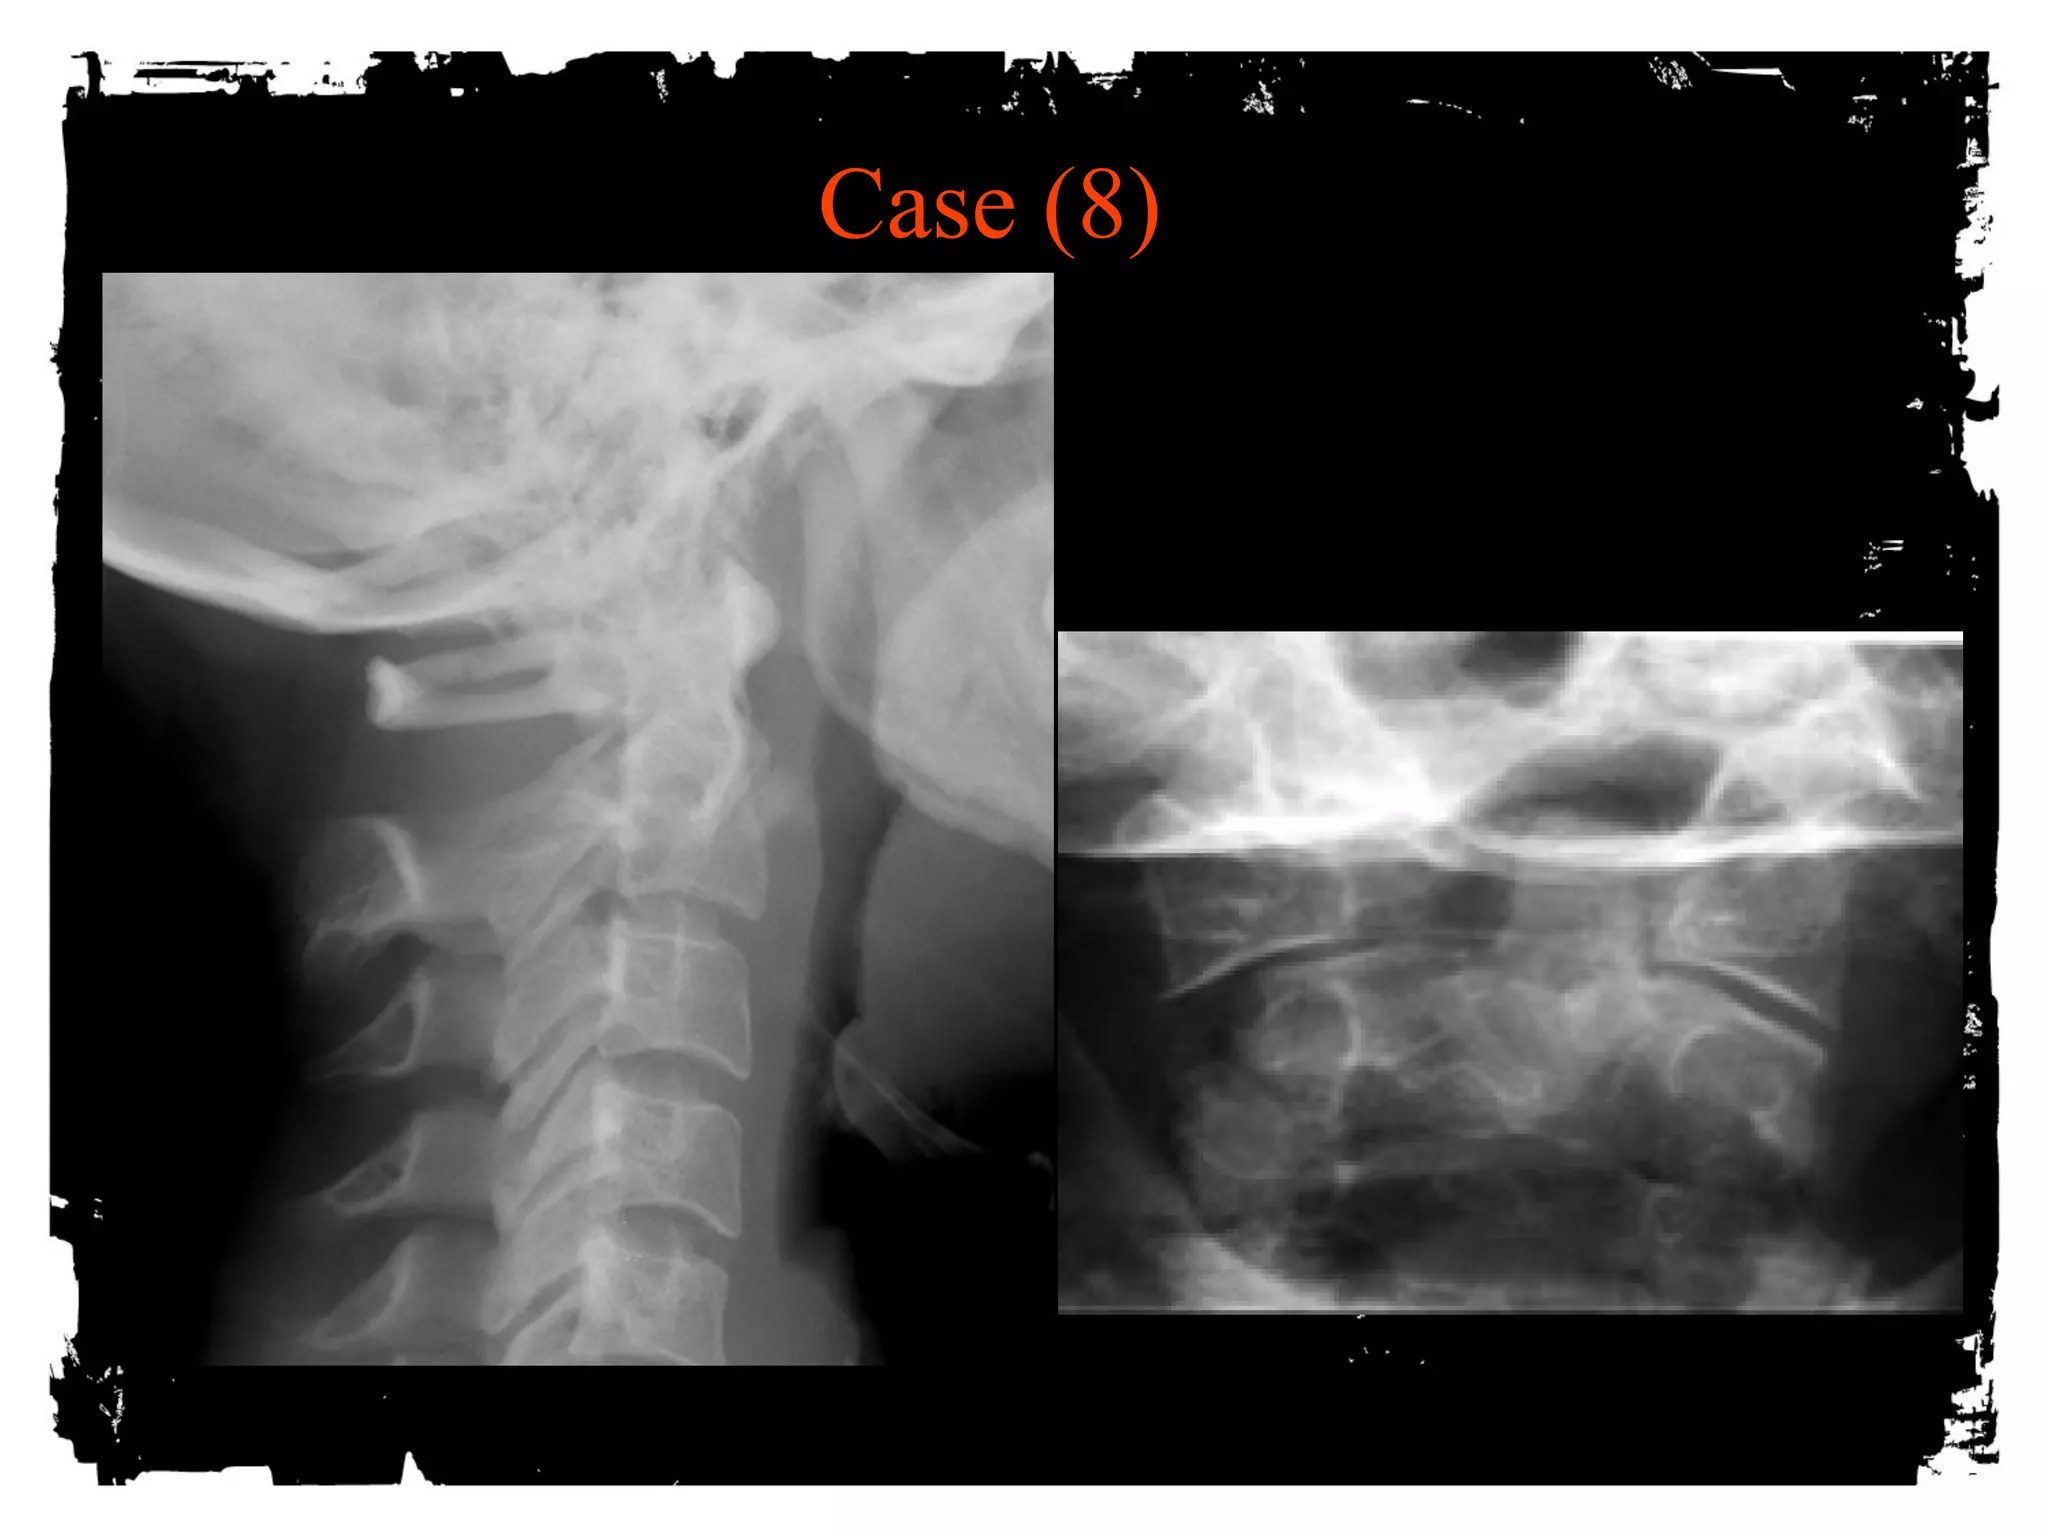

Case (8)

Jefferson Fracture

Burst fracture of ring of C1

Axial loading in the occiput

No associated neuro deficts ( C1 ring is wide!)

> 2mm dislocation of lateral masses of C1 or

odontoid view is diagnostic, 1-2 mm is equivocal

( rotation of head?)

Predental space > 3 mm: disruption of transverse

ligament

1/3 associated with C2 fracture